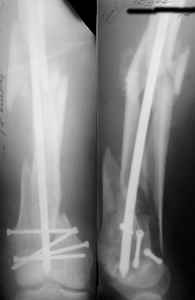

THX, initial images are

1,

2.

At that moment we had in stock only the 10 mm solid nails so of course there was no idea about early weight bearing. But it was quite enough for early knee ROM excersises (see attached). Two locking screws through the distal block provided that.

A new toy is more interesting and fashionable. And anyway it is not panacea, i have already seen presentations with LISS failures like the attached one presented by D.Seligson. And people also demonstrated incisions say that the method is not so LESS invasive as it supposed to be.